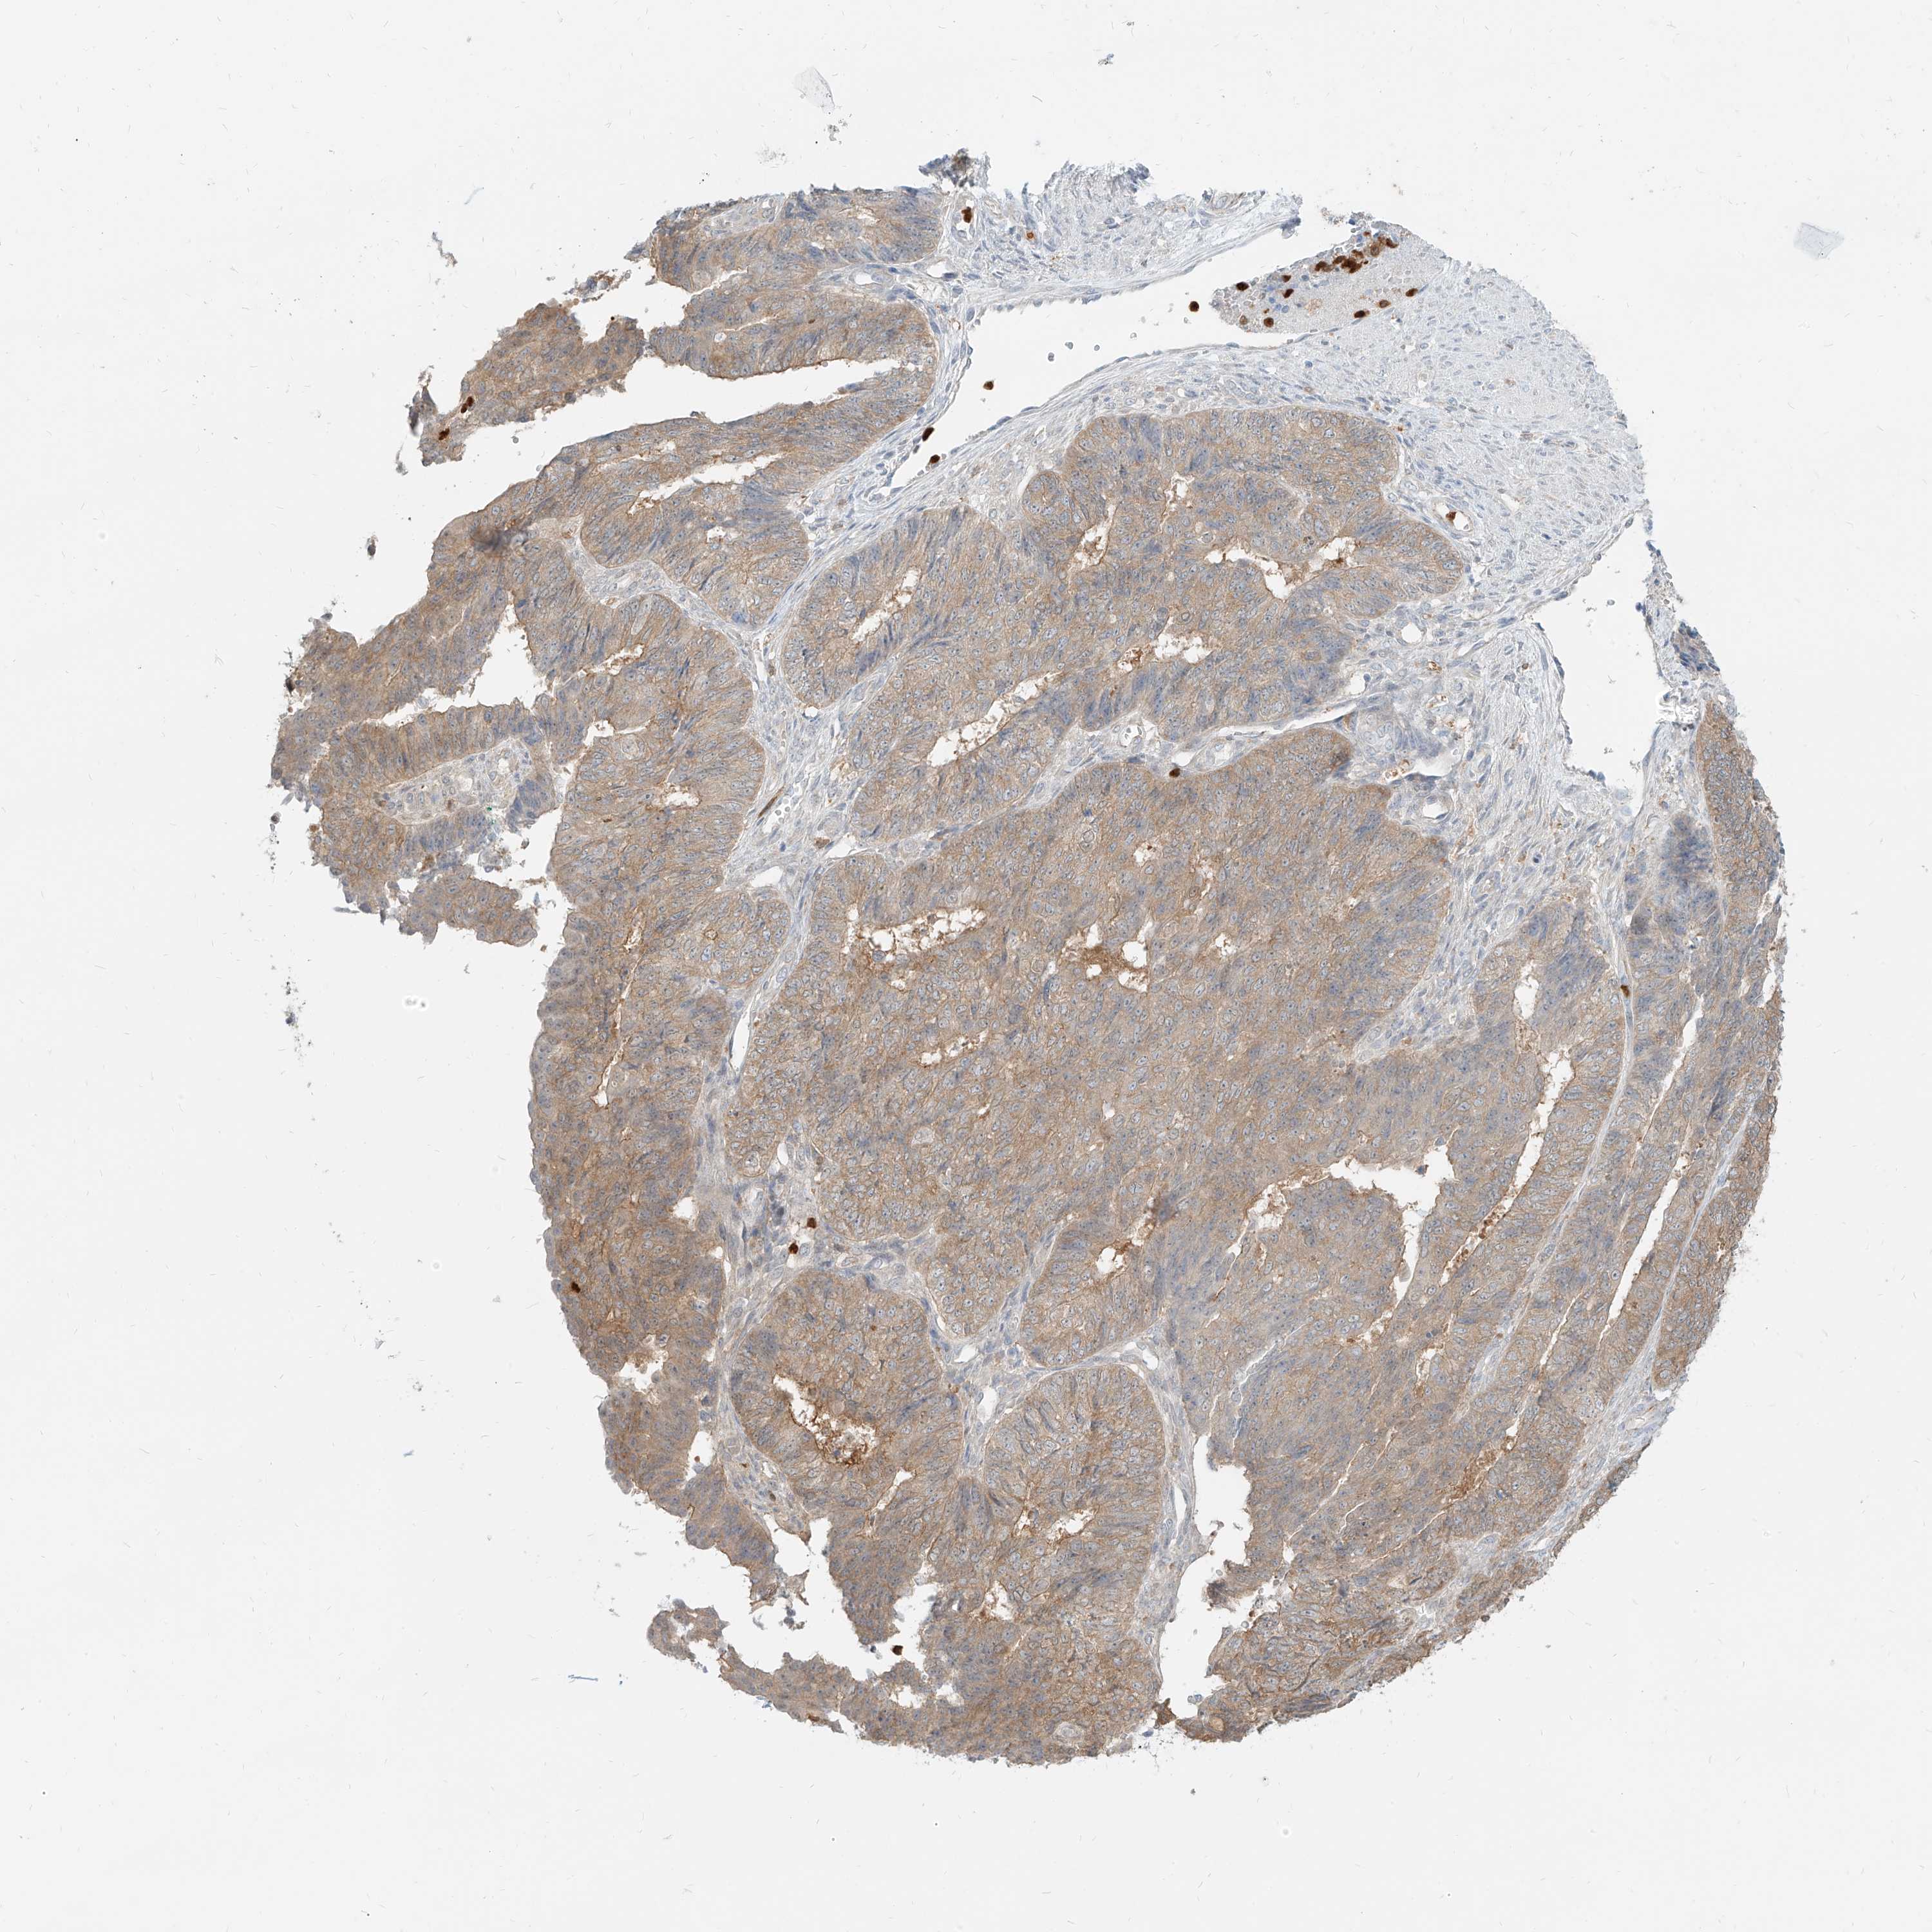

ENDOMETRIAL CANCER - Protein expressioni

A mouse-over function shows sample information and annotation data. Click on an image to view it in a full screen mode. Samples can be filtered based on level of antibody staining by selecting one or several of the following categories: high, medium, low and not detected. The assay and annotation is described here.

Note that samples used for immunohistochemistry by the Human Protein Atlas do not correspond to samples in the TCGA dataset.

Antibody stainingi

Antibody staining in the annotated cell types in the current human tissue is reported as not detected, low, medium, or high, based on conventional immunohistochemistry profiling in selected tissues. This score is based on the combination of the staining intensity and fraction of stained cells.

Each image is clickable and will lead to virtual microscopy that enables deeper exploration of all samples and also displays staining intensity scores, fraction scores and subcellular localization as well as patient and tissue information for each sample.

Antibody HPA031314

Antibody HPA031315

Staining

High

Medium

Low

Not detected

Intensity

Strong

Moderate

Weak

Negative

Quantity

>75%

75%-25%

<25%

None

Location

Nuclear

Cytoplasmic/membranous

Cytoplasmic/membranous,nuclear

Adenocarcinoma, NOS

Adenocarcinoma, metastatic, NOS